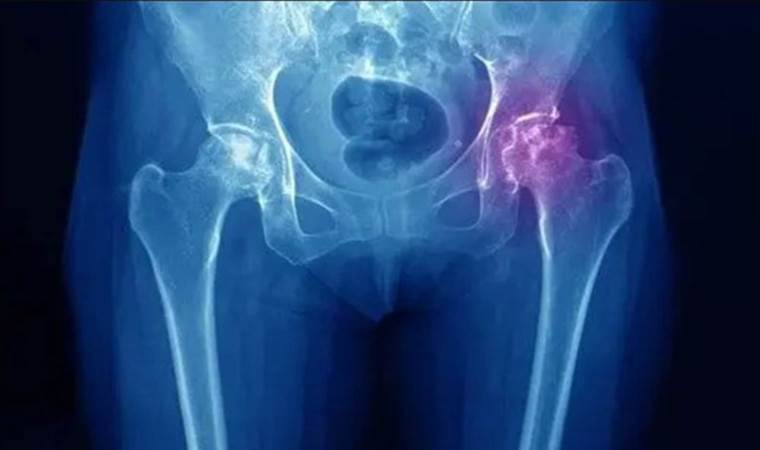

Kalça avasküler nekrozu, kalça kemiğinin kan akışının azalması veya tamamen kesilmesi nedeniyle oluşan bir durumdur. Doç. Dr. Kurnaz, bu durumun kan dolaşımındaki sorunlar, kan damarlarındaki tıkanıklıklar, yaralanmalar, travmalar veya uzun süreli steroid kullanımı gibi etkenlerle ortaya çıkabileceğini belirtti.

Hastalığın belirtileri arasında en yaygının kalçada şiddetli ağrı olduğunu ve bununla birlikte kalça hareketlerinde kısıtlılık ya da zorlanma hissi ile ilerleyen aşamalarda topallama görülebileceğini ifade eden Doç. Dr. Kurnaz, hastalıktan korunmak için düzenli egzersiz, dengeli beslenme, steroid kullanımını sınırlama ve travmalardan kaçınmanın önemli olduğunu vurguladı. Ayrıca, kalça avasküler nekrozunun erken tanının tedavi seçeneklerini artırabileceğini ve belirtiler fark edildiğinde uzman bir hekimle görüşmenin önemli olduğunu belirtti.

Tedavi planının hastadan hastaya farklılık gösterebileceğini belirten Doç. Dr. Kurnaz, cerrahi seçenekler arasında kemik grefti, dirilleme (core decompression), osteotransfer (vaskülerize kemik grefti), kök hücre tedavisi ve artroskopik debridman gibi yöntemleri sıraladı. Erken evrede fark edilip tedavi edilmeyen durumlarda ise kalça protezinin hastanın ağrısız bir yaşam sürmesine yardımcı olabileceğini ifade etti.